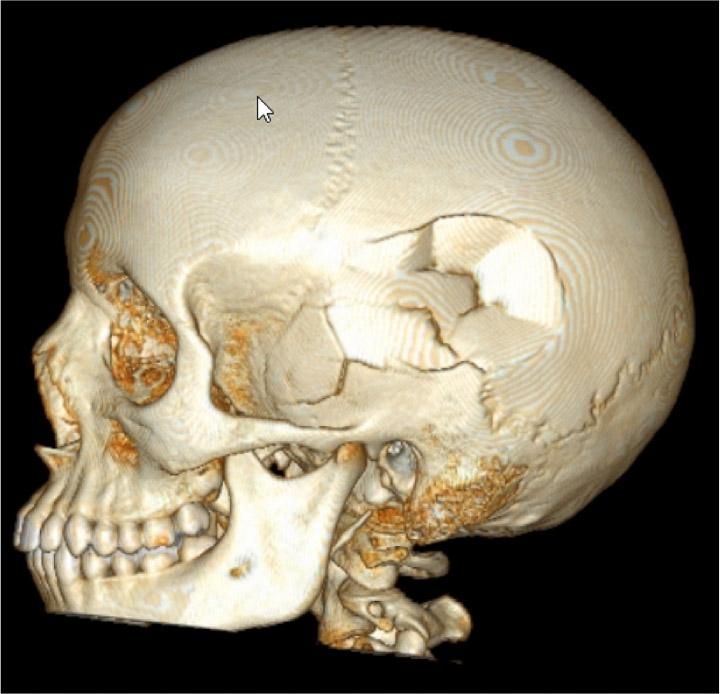

- Acute conditions including infection, trauma

- Brain and spine tumors